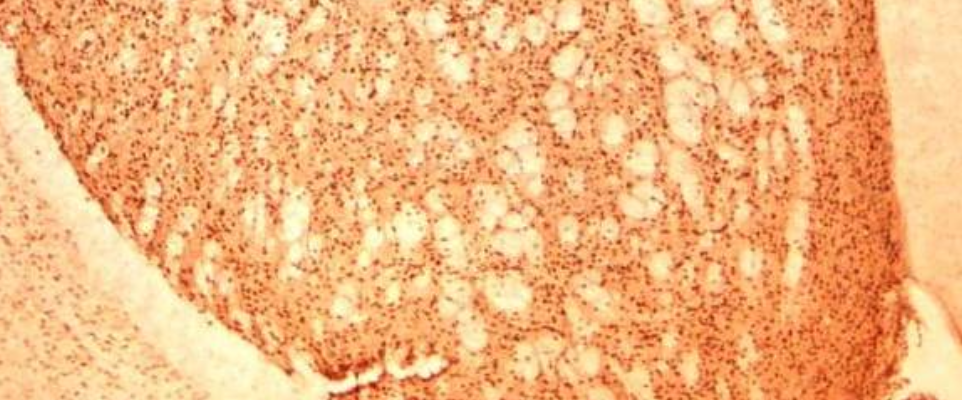

This image shows the brain of a mouse model of Huntington's disease.